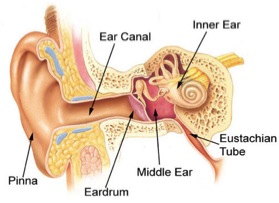

And, because COVID-19 causes inflammation in the nose and nasopharynx (the upper part of the throat located behind the nose), the Eustachian tube (the tube that connects the nose and middle ear) may also become inflamed during the course of the infection and lead to middle ear congestion.

This pain in throat and ear can be present due to a variety of causes ranging from common cold, cough to tonsillitis or an ear infection. In humans, the throat is connected to the middle ear canal by a small tube-like structure called the Eustachian tube.

Why do Eustachian tubes swell?

What happens if you have a blocked eustachian tube?

What is the tube that connects the back of the nose to the middle ear?

Eustachian Tube Blockage. The eustachian tube is a narrow tube that connects the back of the nose to the middle ear. It protects the middle ear from bacteria and viruses, keeps air pressure equal in the middle ear space, and helps drain secretions from the middle ear .

Why does the eardrum work?

It helps regulate the pressure inside the ear so that it matches the air pressure outside , enabling the eardrum to function properly. Sometimes there is an imbalance in pressure, which may result from a blocked eustachian tube or a change in air pressure or altitude.

Why does my ear hurt?

Sharp ear pain often results from pressure changes or infections. Below are some causes of a sharp pain in the ear. The pain may result from one or a combination of these factors. Each ear contains a narrow tube called a eustachian tube.